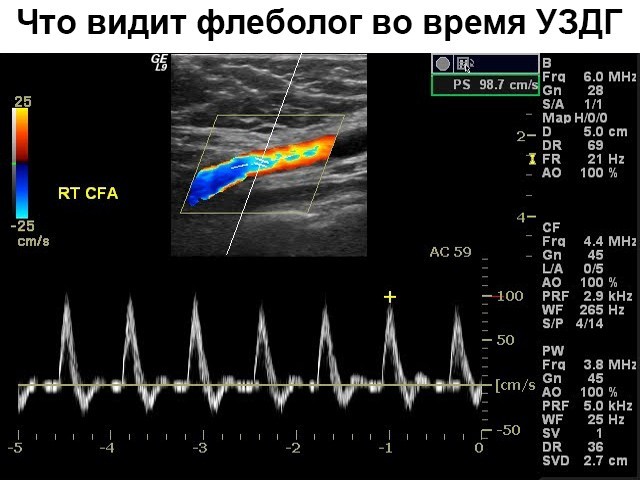

УЗДГ, так сокращенно называется двухмерная допплерография, – классический диагностический вариант сосудов ног, дающий возможность определять главные параметрические элементы кровяного тока и его скорости. Обычно применяется для определения сосудистых патологий.

Изображение, которое получает флеболог, является трехмерным. На нем хорошо можно диагностировать любую патологию кровеносных сосудов конечностей.

Если сделать УЗДГ вен нижних конечностей, это поможет проанализировать степень проходимости сосудов, узнать скорость кровотока.

При помощи УЗДГ сосудов ног проверяют проходимость глубоких и поверхностных вен, дают оценку состояния клапанной венозной системы.